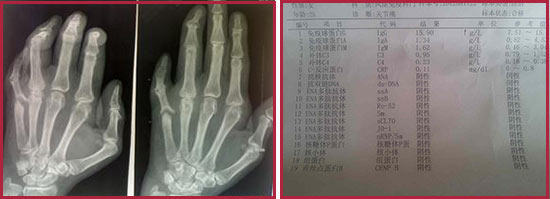

(圖:類風(fēng)濕性關(guān)節(jié)炎常規(guī)檢查和X線檢查結(jié)果)

、X光片檢查:早期X線可以看到受累關(guān)節(jié)周圍軟組織腫脹,晚期為關(guān)節(jié)半脫位、畸形及強(qiáng)直。

第二、類風(fēng)濕因子:對(duì)于診斷具有比較重要的參考價(jià)值。但是類風(fēng)濕因子陰性不能排除本病的可能,須結(jié)合臨床。

第三、C反應(yīng)蛋白及血沉:C反應(yīng)蛋白與病情活動(dòng)指數(shù)、晨僵時(shí)間、握力、關(guān)節(jié)疼痛及腫脹程度、血沉和血紅蛋白水平密切相關(guān),病情緩解時(shí)C反應(yīng)蛋白下降,反之則上升。C反應(yīng)蛋白水平持續(xù)不降多提示病變的進(jìn)展,病情加重則血沉加快,病情緩解時(shí)可恢復(fù)至正常,但約有5% 的類風(fēng)濕關(guān)節(jié)炎患者在病情活動(dòng)時(shí)血沉并不增快。

第四、血常規(guī):類風(fēng)濕性關(guān)節(jié)炎患者可伴有貧血,白細(xì)胞數(shù)大多正常,在活動(dòng)期可略有增高。貧血和血小板增多癥與疾病的活動(dòng)相關(guān)。多數(shù)病例的紅細(xì)胞沉降率在活動(dòng)性病變中常增高,可為疾病活動(dòng)的指標(biāo)。血清鐵、鐵結(jié)合蛋白的水平常減低。